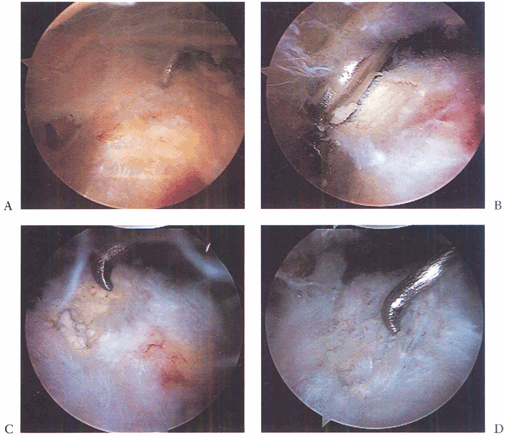

Figure 79.20. Calcific tendinitis. A: Note inflamed area on bursal surface of the supraspinatus, which corresponds to an underlying calcific deposit. B: Unroofing of the calcific deposit by gentle shaving. C: Full extent of the deposit. D: After complete debridement, the tendon remains intact. (This figure is printed in black and white as Figure 20 of Chapter 79.)